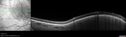

61 year old man with amelanotic choroidal nevus. Vision Normal - Stable over 4 years.

Amelanotic Choroidal Nevus - Multimodal Imaging577 views61 year old man with amelanotic choroidal nevus. Vision Normal - Stable over 4 years.00000